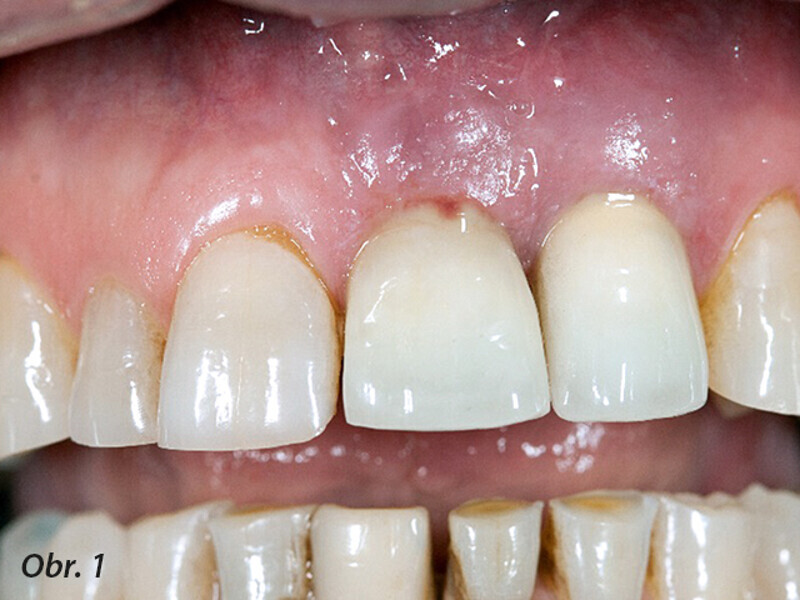

Terapie periimplantitidy při použití resorbovatelného, náhradního kostního materiálu